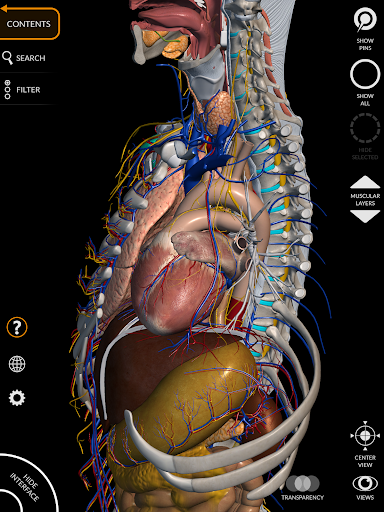

يتيح لك "Anatomy 3D Atlas" دراسة التشريح البشري بطريقة سهلة وتفاعلية.

من خلال واجهة بسيطة وبديهية، من الممكن ملاحظة كل بنية تشريحية من أي زاوية.

تتميز النماذج التشريحية ثلاثية الأبعاد بتفاصيل خاصة ودقة تصل إلى 4K.

يسهل التقسيم حسب المناطق والمناظر المحددة مسبقًا مراقبة ودراسة الأجزاء الفردية أو مجموعات الأنظمة والعلاقات بين الأعضاء المختلفة.

نماذج تشريحية ثلاثية الأبعاد

• الجهاز العضلي الهيكلي

• الجهاز القلبي الوعائي

• الجهاز العصبي

• الجهاز التنفسي

• الجهاز الهضمي

• تدوير وتكبير كل نموذج في مساحة ثلاثية الأبعاد

• خيار إخفاء أو عزل نموذج واحد أو نماذج متعددة مختارة

• وظيفة الشفافية

• تصور العضلات من خلال مستويات الطبقات من الطبقات السطحية إلى الأعمق